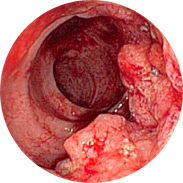

Upala i suppuracija sluznice rektuma

Krvarenje može dovesti do anemije

Povećanje tjelesne temperature, s jakom upalom, može dovesti do vrućice.

A najgora stvar je rak rektuma! Opsežna klinička ispitivanja Hemorena provedena su u Hrvatskom medicinskom centru (Zagreb) 2016. godine. Ukupno je u istraživanjima sudjelovalo više od 1000 muškaraca i žena s hemoroidima različitog stupnja. Svi ispitanici koristili su Hemoren kremu 3 tjedna. Čak su i liječnici bili zapanjeni rezultatima studije!